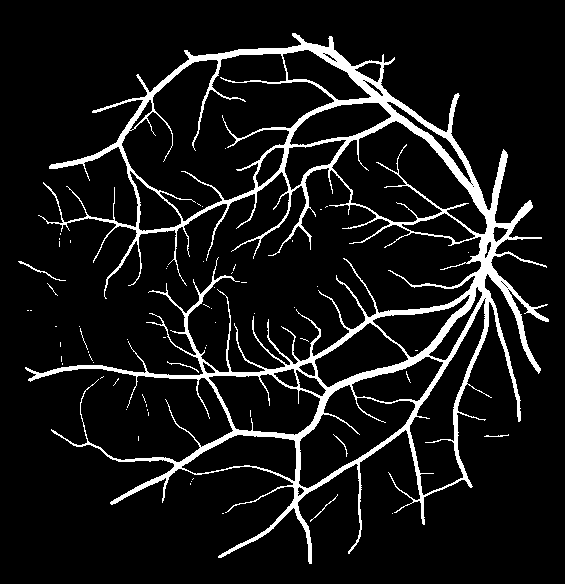

Table V presents quantitative performance benchmarks of SegRAVIR and other competing approaches for retinal artery and vein classification on the RITE dataset [11]. SegRAVIR outperforms previous state-of-the-art approaches in terms of accuracy, sensitivity, and specificity. Fig. 5 provides a qualitative comparison between segmentation outputs of SegRAVIR and the method of Hemelings et al. [40] on the RITE test set.